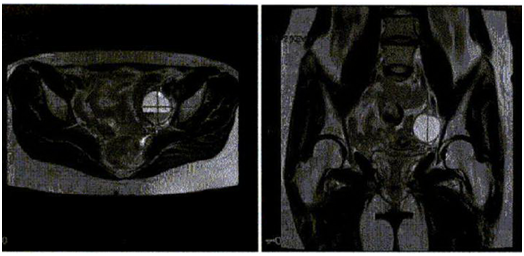

Physical exam revealed vital signs within normal limits, and BMI of 23.35 kg/m2. Positive findings included pain on palpation of a bladder nodule and a left vaginal fornix nodule. There were no palpable adnexal masses; rectal exam was within normal limits. A hysterosalpingogram (HSG) one year prior had shown bilateral tubal patency and no uterine filling defects. Her most recent transvaginal ultrasound showed adenomyosis. Pelvic MRI showed a 3.8 cm complex, septated, low signal intensity, non-enhancing lesion arising from the left adnexa, possibly representing an endometrioma. There are epithelial changes along the bladder and uterosacral ligaments with no evidence of endometriosis (Figure 1).

Figure 1 Pelvic MRI showed a 3.8 cm complex septated low signal intensity non-enhancing lesion arising from the left adnexa, possible representing and endometrioma. There are epithelial changes along the bladder and uterosacral ligaments with no evidence of endometriosis.